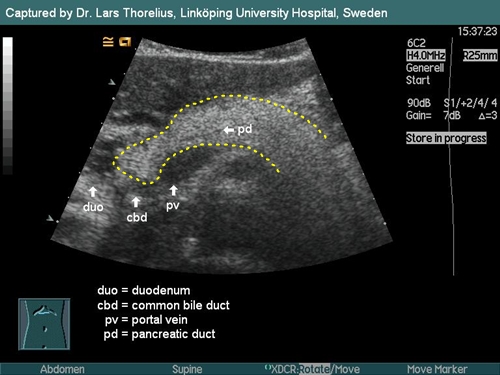

При ультразвуковом исследовании железы сравнивают ее эхогенность в норме с эхогенностью области печени. Обычно поджелудочная железа должна быть немного светлее печени и иметь четкие гладкие контуры. Если на стенограмме видны неровные края с неровной поверхностью и размытые очертания органа, это может указывать на повышенную эхогенность и структурные и функциональные нарушения органа.